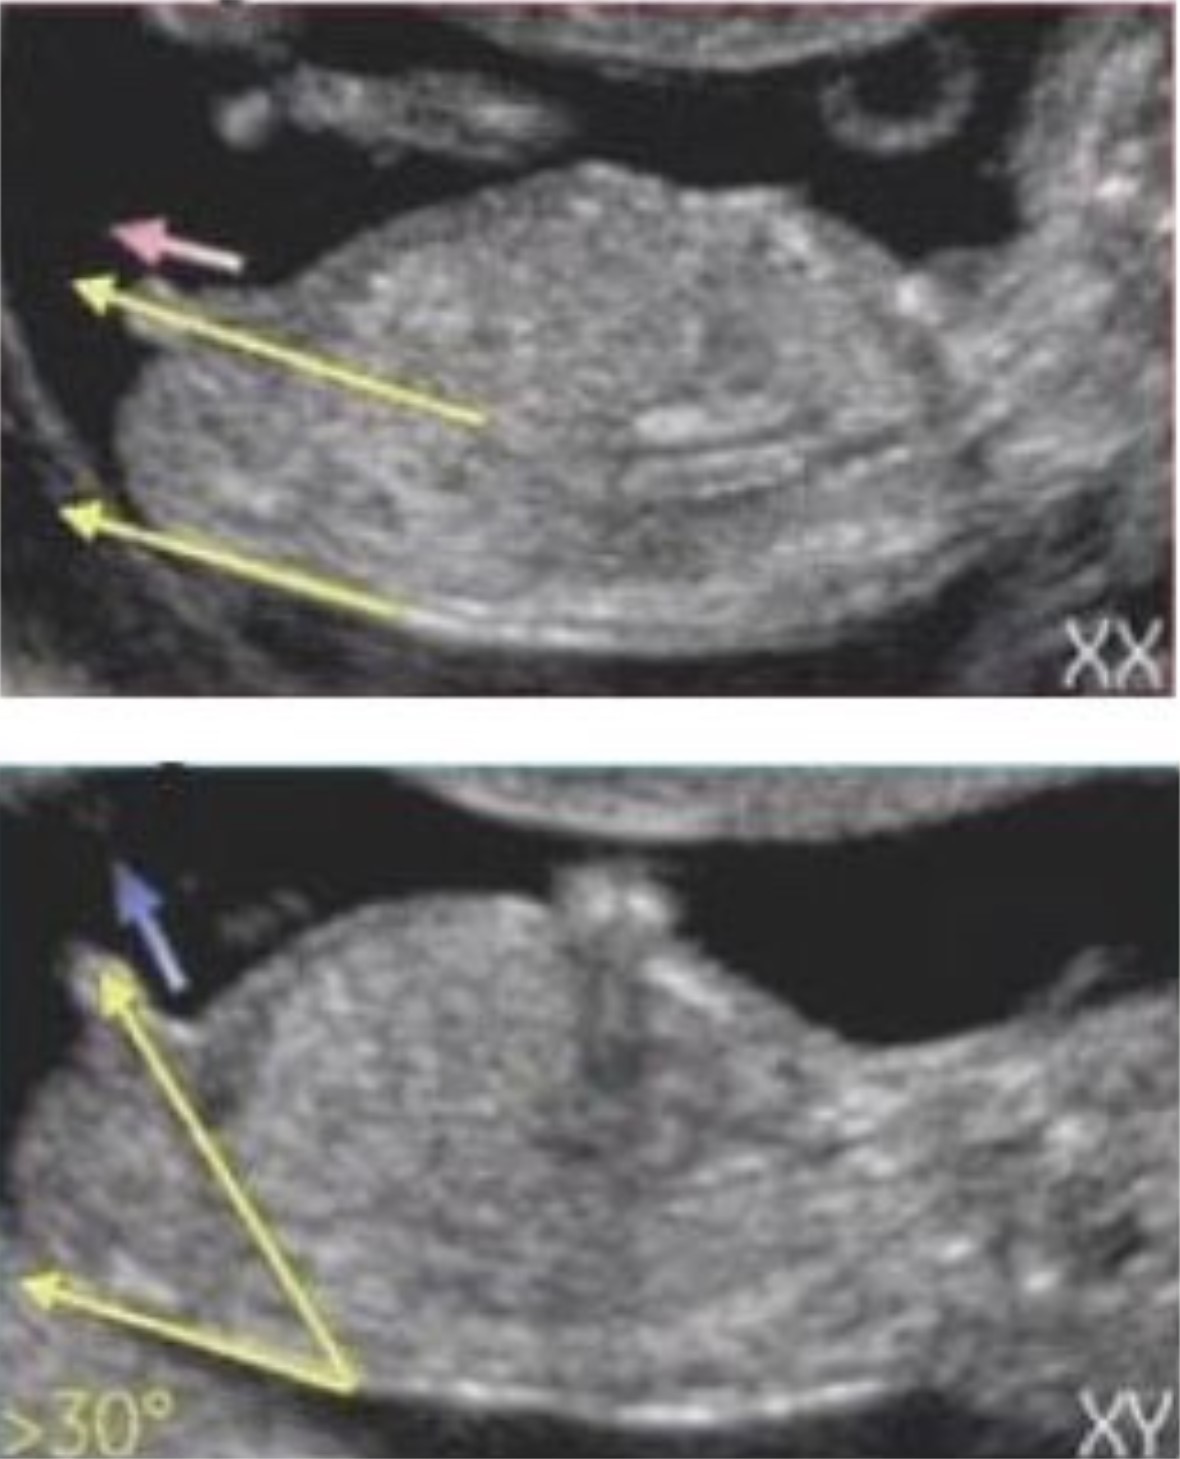

태아 초음파에서 옆모습의 척추와 성기의 각도를 통해 볼 수 있는 방법을 12주 각도법이라고 부릅니다. 12주보다 좀 더 이르면 애매할 수도 있고, 12주가 지나면 성기의 형태로도 추정할 수 있기 때문에 가장 빠르게 성별을 확인할 수 있는 방법입니다. 툭 튀어나온 부위가 척추와 평행을 이루고 있다면 딸, 30도정도의 각도를 이루고 있다면 아들이라고 합니다. 16주 이상 됬을 때 정확한 성별을 판단하기 이전에 가장 정확하게 확인 할 수 있는 방법입니다.

처음말씀드린 바와 같이 16주~20주가 되면 아이의 성별은 병원에서도 확인 가능합니다.(일부 병원은 성별에 대한 언급은 안 해준다고 합니다.) 제가 테스트했던 4가지 방법 중 난황을 제외하고는 딸로 모두 적중했습니다. 16주가 되었을 때 아래 사진과 같이 남아와 여아의 성기가 변화되기 때문에 엉덩이 사진만으로도 성별 확인이 가능하답니다.